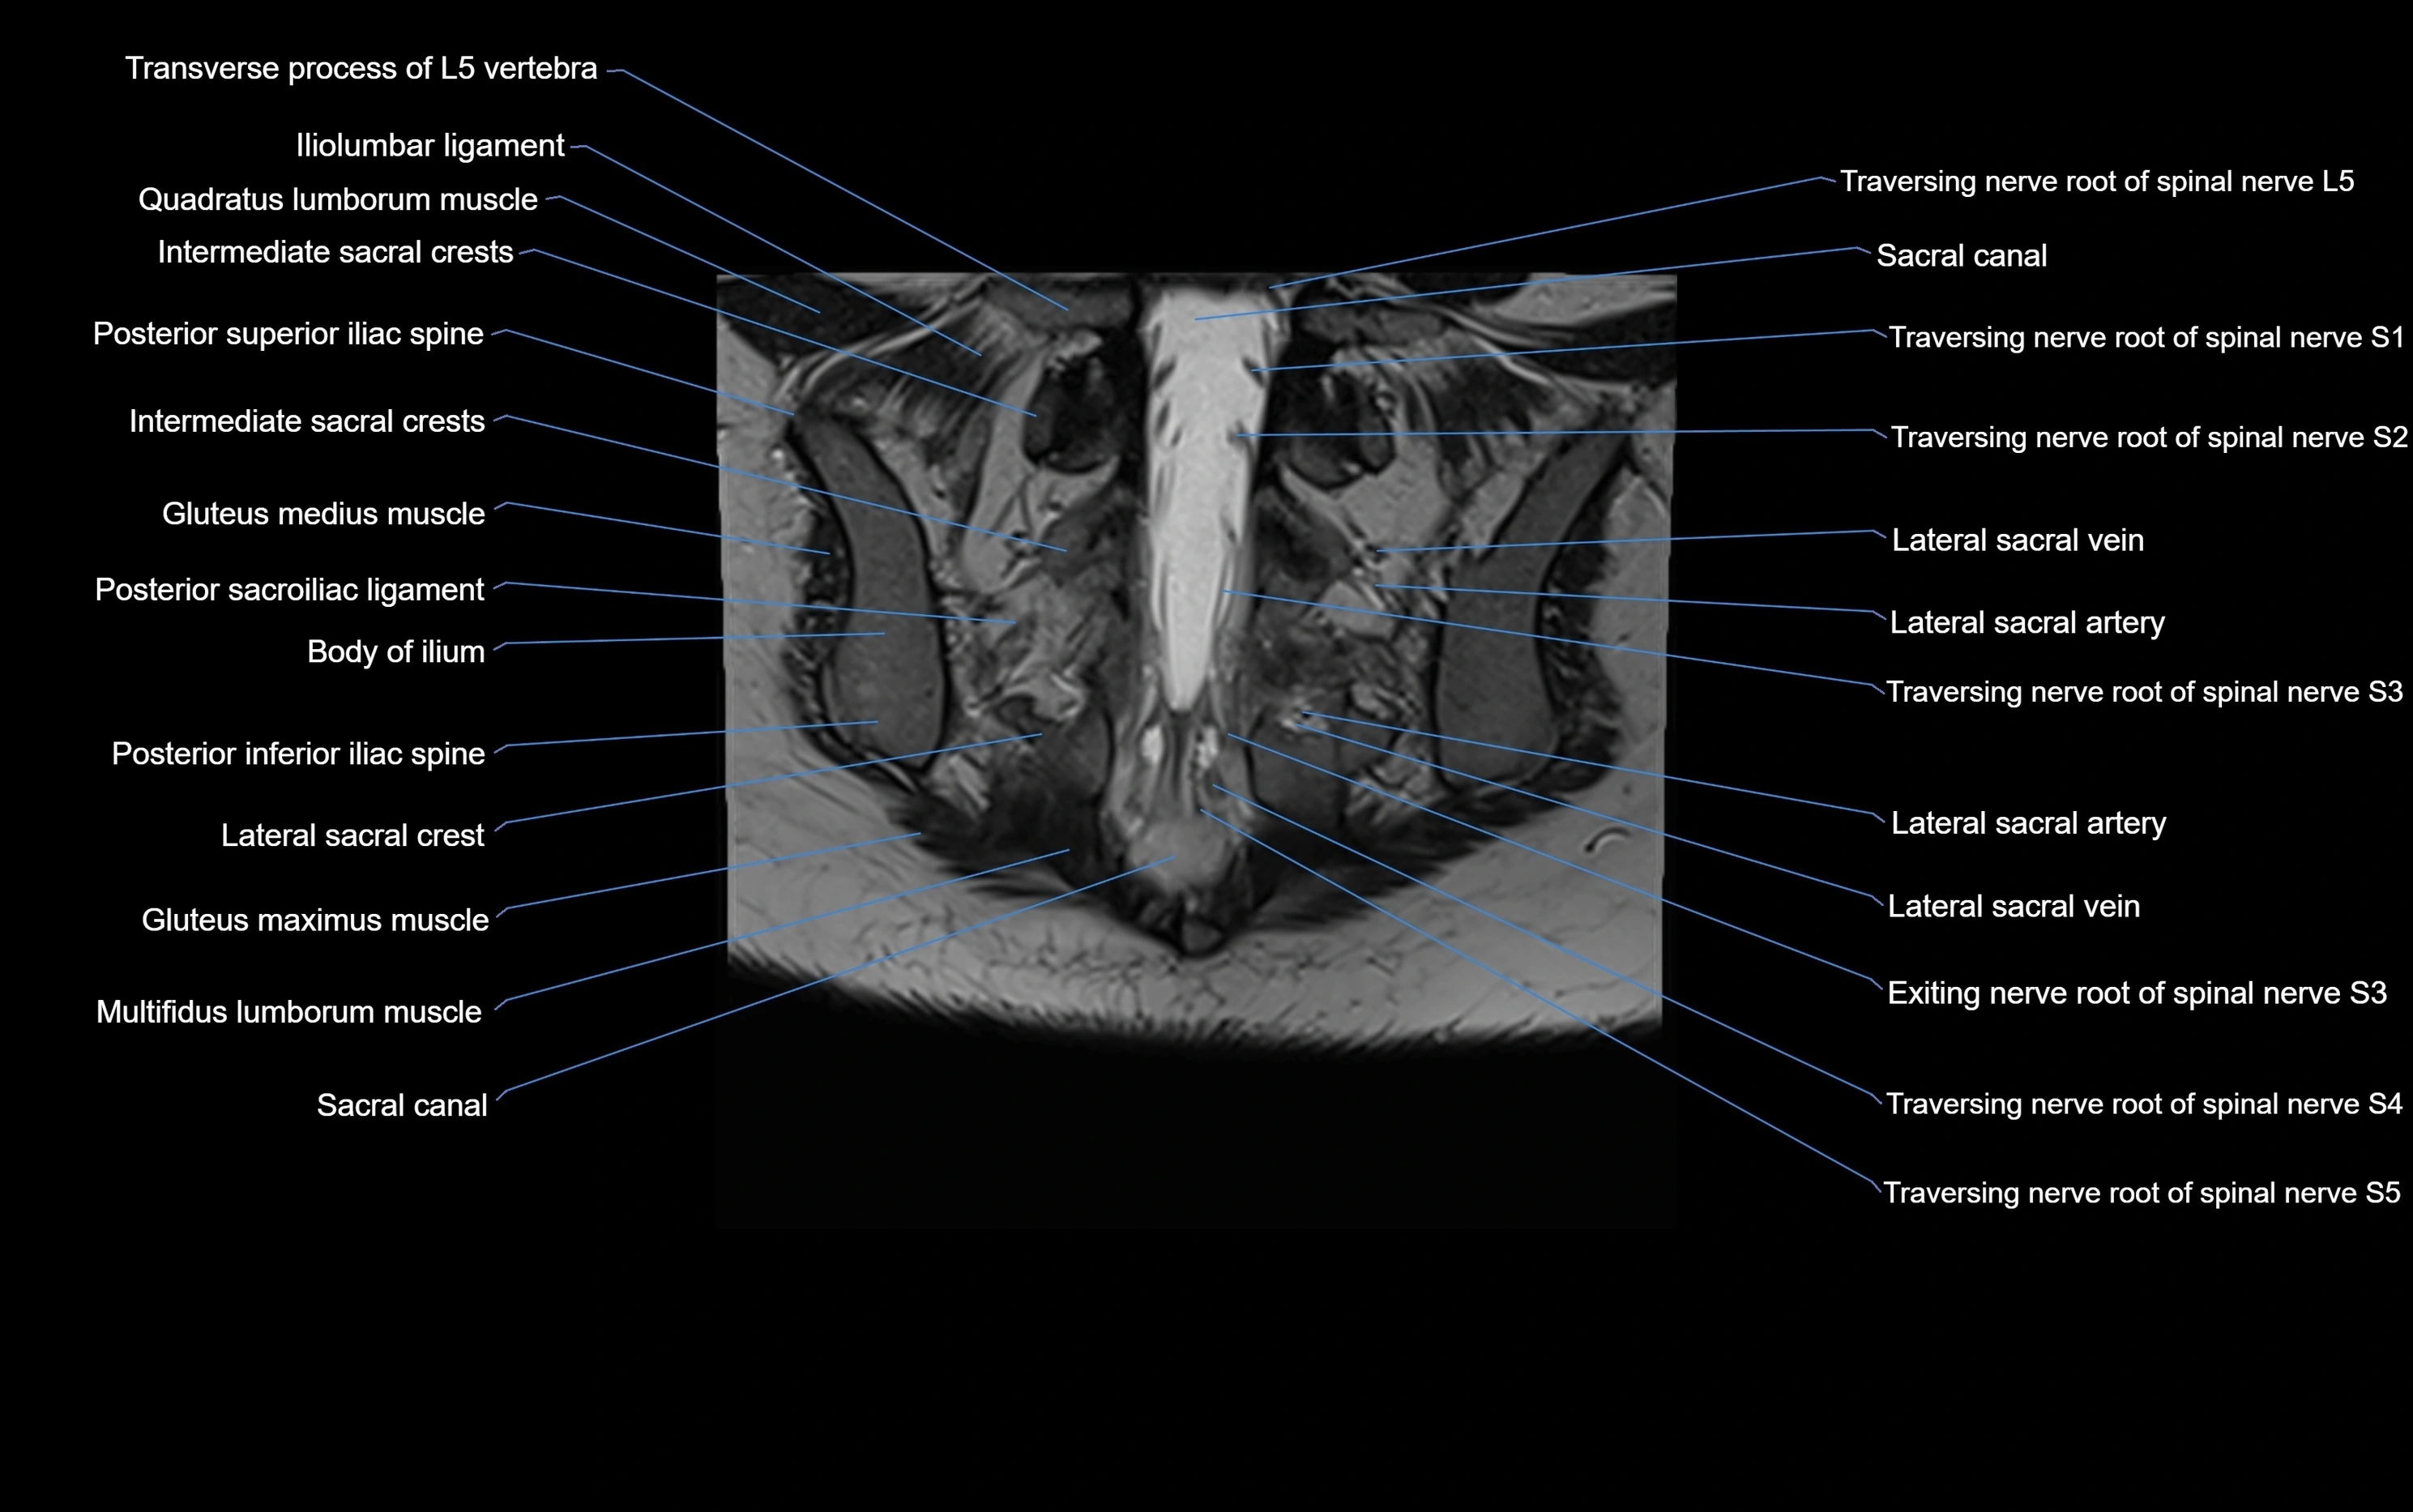

CT image

image